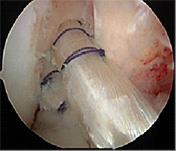

自分の組織を用いて再建する(自家腱移植)のがベストな方法とされています。当院で行っている膝屈筋腱(ハムストリングス)を用いた関節鏡視下膝前十字靱帯再建術は、切開は最小限で大きな合併症がなく、術後の成績も安定しているため、有効な治療方法として確立されています。 手術は膝関節を構成する大腿骨と脛骨の最適部位に関節鏡を用いて細いトンネルを作製し、そこに採取加工した腱を貫いて上端と下端を金具で固定することで膝の安定性を得ることを目的とし、全身麻酔+硬膜外持続麻酔下で行います。尚、本院では遺残靱帯(レムナント)が残存している患者様に対しては再生医療の観点※からレムナントを切除せずレムナントを利用し一重束前十字靱帯再建術(レムナント温存法)を、また女性で膝が柔らかい患者様(反張膝の患者様)などには二重束前十字靱帯再建術を、また二度目の受傷の患者様などには膝蓋腱を用いて一重束前十字靱帯再建術(BTB法)をおこなっています。また、縫合可能な半月板損傷がある患者様に対しては全例半月板縫合を行います。(Biomet MaxFire™ を利用し、関節内だけの操作で縫合します。)手術時間はレムナント温存法で行った時は約1時間から1時間半です。

2重束ACL再建後の前十字靱帯